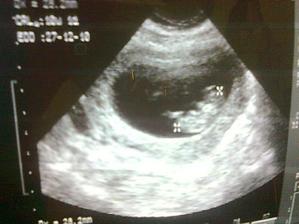

Náš anjelik🙂